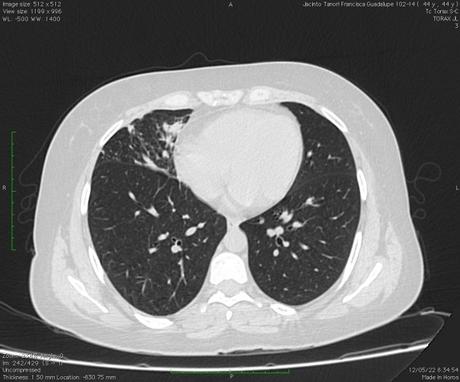

Vía aérea y pulmones: Con ventana para pulmón se observa hacia el segmento superior del lóbulo inferior derecho la presencia de una lesión cavitada, la cual tiene un diámetro máximo de 3.3 cm, además ambos pulmones presentan algunas áreas con patron micronodular, predominantemente hacia lóbulos medio y língula. La tráquea se aprecia central, sin alteraciones.

- ESTUDIO TOMOGRÁFICO DE TORAX QUE MUESTRA HALLAZGOS QUE PUDIERAN CORRESPONDER CON PROCESO INFECCIOSO DE TIPO GRANULOMATOSO NO TUBECULOSO (MICOBACTERIUM AVIUM) COMO PRIMERA POSIBILIDAD, SIN EMBARGO, LA POSIBILIDAD DE QUE PROCESO TUBERCULOSO O FIMICO NO PUEDE SER DESCARTADO.